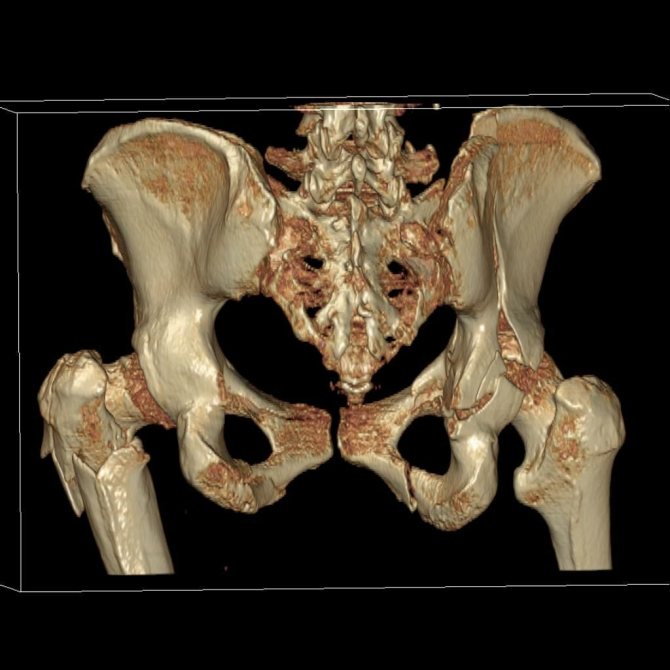

КТ.

В чем основные различия между КТ и МРТ? Магнитно-резонансная томография позволяет выявить повреждения суставной капсулы, связок и мягких тканей. На компьютерных томограммах хорошо визуализируются мелкие костные дефекты, которые не видны на рентгене.